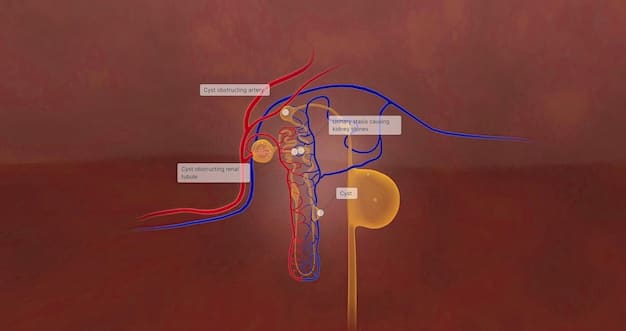

Prostatitis is the inflammation of the prostate gland, often caused by bacterial infection. Symptoms include pelvic pain, urinary problems, and sexual dysfunction.

- Testicular Cancer: A malignant tumor in one or both testicles.

- Benign Prostatic Hyperplasia (BPH): Enlargement of the prostate gland, causing urinary symptoms.

Early detection and appropriate treatment are crucial for managing these conditions and improving overall health.

In summary, being aware of common health issues affecting the male anatomy is essential for early detection and effective management. Regular check-ups and prompt medical attention can significantly improve outcomes.